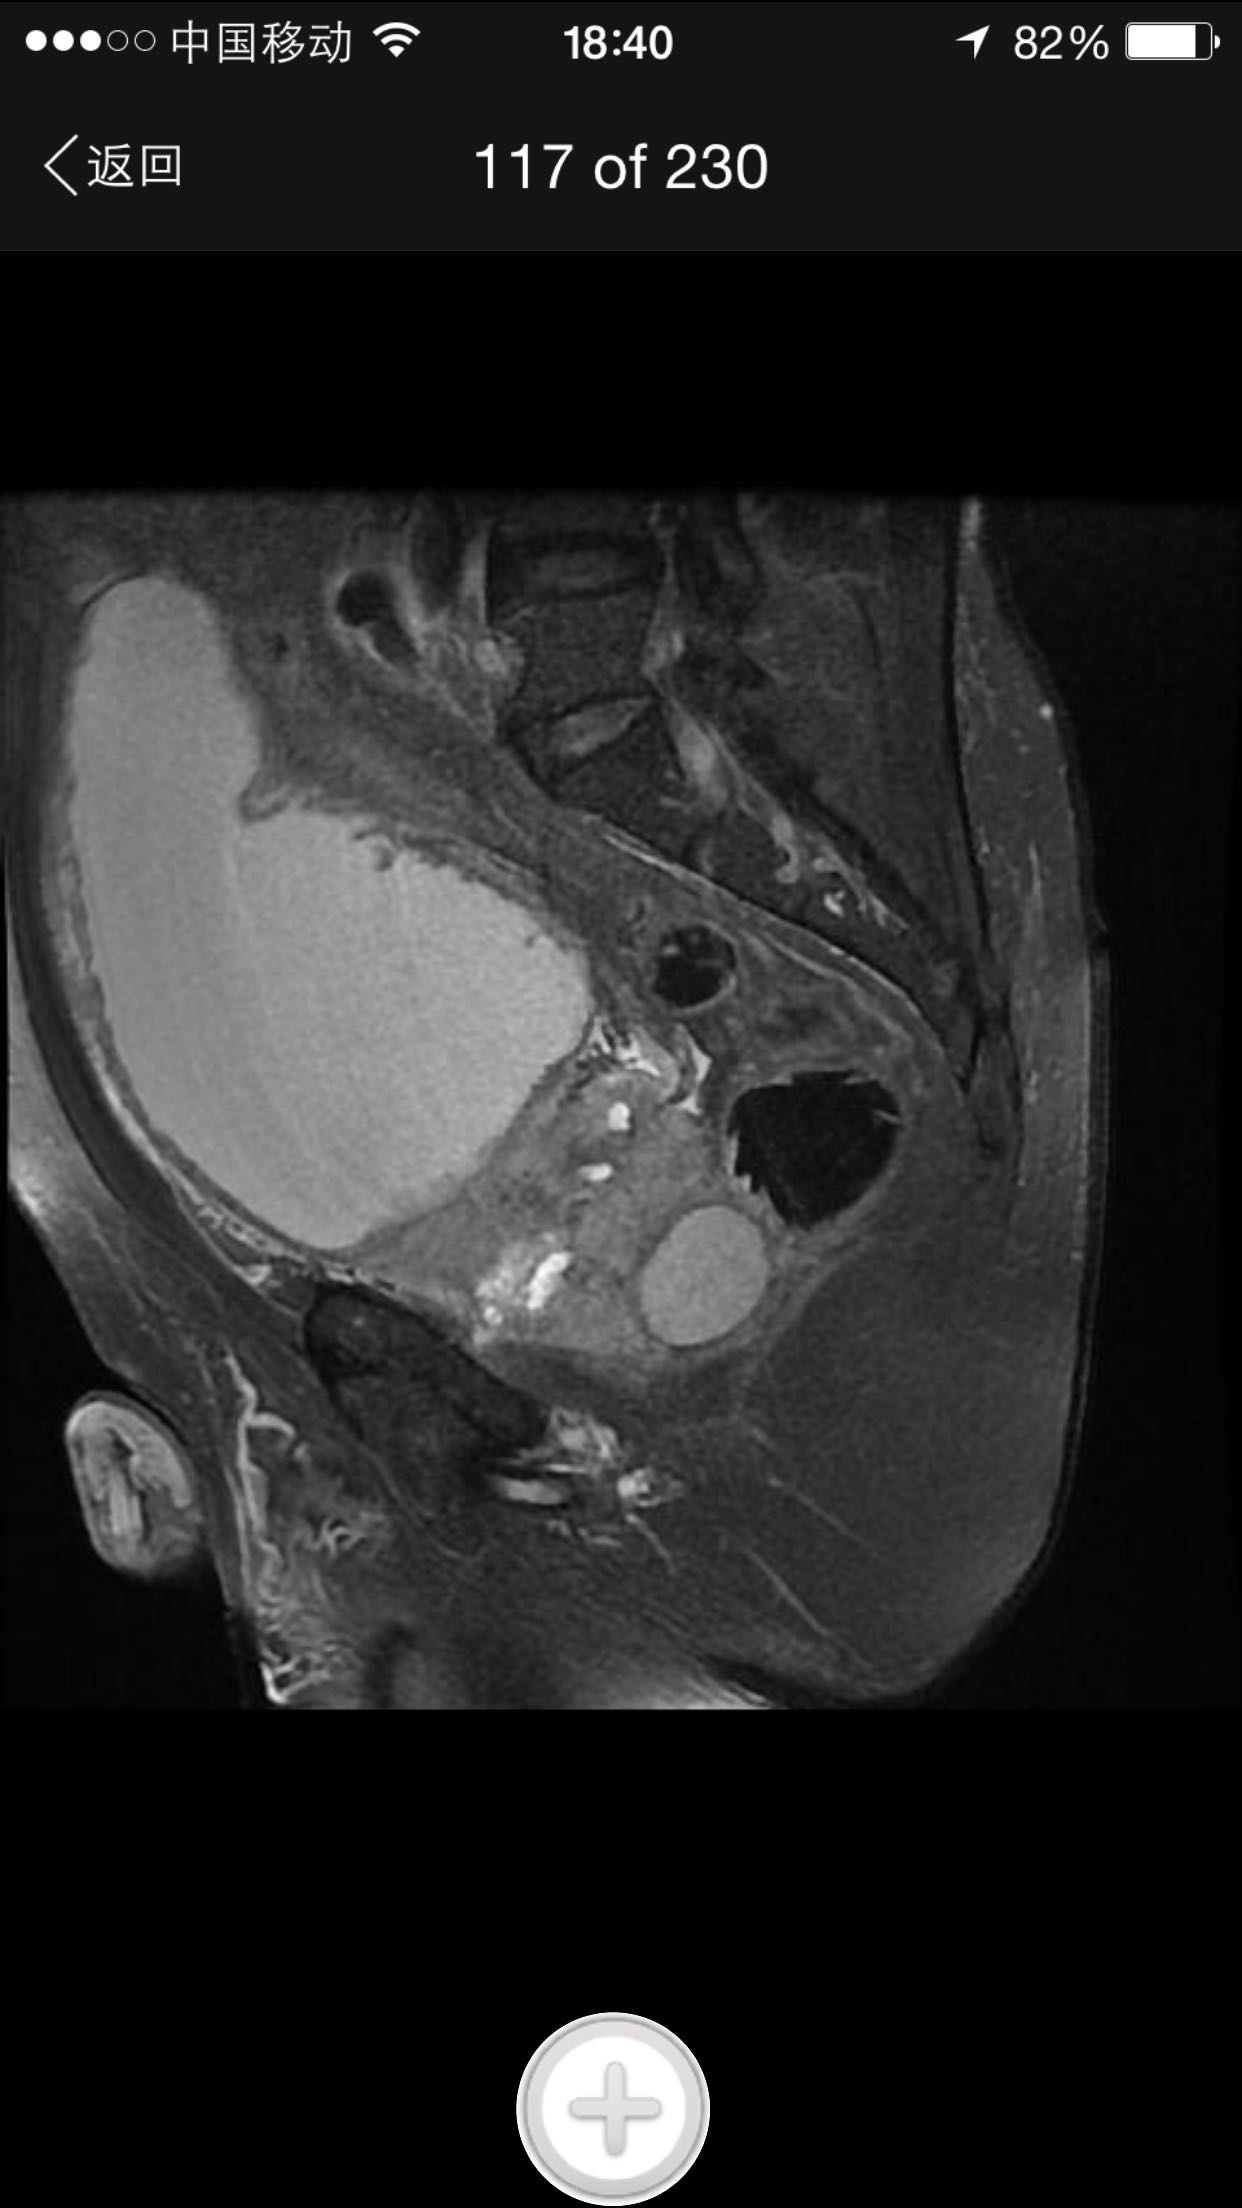

肛诊:前列腺增大,质硬,可扪及多个硬结。 PSA329ng/ml。

诊断:前列腺癌晚期 尿潴留 治疗:考虑患者临床分期较晚,T4期,且淋巴结转移,合并尿潴留,超声提示肾积水,决定行TURP,解决排尿困难。术中快速,如为前列腺癌,直接行手术去势。术中按上述方案处理。术后病理为前列腺中分化腺癌。